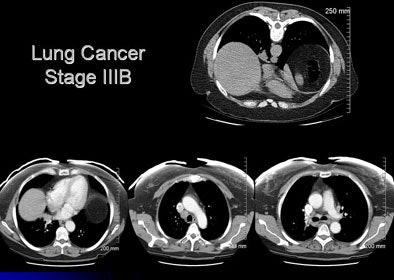

![]() |

| CT images of a 54-year-old woman revealed an opacity at the right lung base. The radiologist recommended a dedicated chest CT, which revealed abnormalities in the mediastinum; the patient subsequently underwent PET, and a biopsy confirmed lung cancer, stage IIIa. The patient was doing well following surgery, chemotherapy, and radiation. |